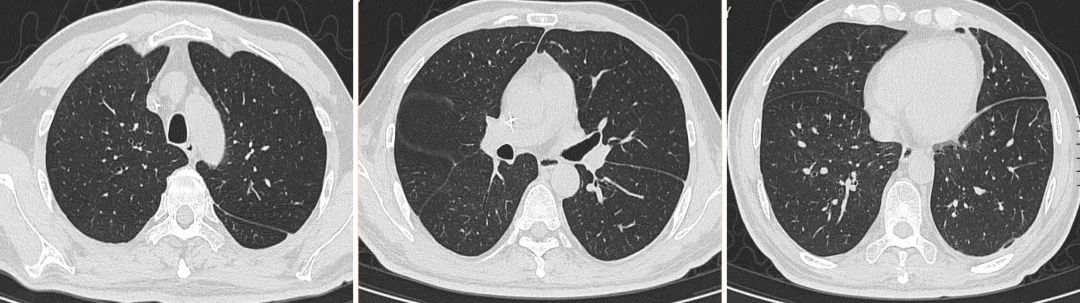

再次调整治疗方案:加用复方磺胺甲噁唑片 0.96g 口服 tid、卡泊芬净 50mg 静滴 qd抗真菌治疗。当天夜间体温即恢复正常。继续加强支持治疗等。10.13,胸部CT复查 双肺野清晰,胸水吸收。

5、第五阶段:PJP及腹腔感染好转,放疗阶段:

2020.09.11 PET-MRI:1、淋巴瘤术后化疗后,左心膈角区团块状软组织异常信号影,FDG代谢异常增高,考虑局部活性肿瘤病灶, 2、左膈肌增厚FDG代谢增高伴左膈下积液,考虑炎性病变伴包裹性积液;胰尾旁包裹性积液。3、右肺炎症。根据该结果,考虑膈下淋巴瘤复发。由于当前PJP控制可,经与放疗科、肿瘤科多学科讨论后,拟对膈下活性肿瘤病灶行放疗。2020.10.29 放疗25次后结束出院。

【图8】经治疗后,10.13复查胸部CT扫描结果

【图9】典型的非HIV患者PJP的HRCT表现。A:冠状面HRCT图像重新格式化突出了上叶的主要受累。B:HRCT显示双侧对称毛玻璃样浑浊,胸膜下区域分布为主,但胸膜下豁免征。C和D 不典型PJPHRCT :C:结节样;D:囊样表现。引自参考文献2.